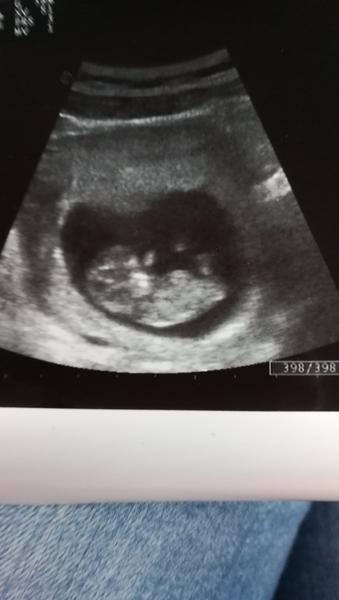

@natalia137 Gratulujem a uzivaj pocity stastia 😉 ...Prve kontroly a prve fotky a bijuce srdiecko su najkrajsie okamihy v zivote zeny...Hned za tym kopanceky Tvojho drobceka, ked pridu, budes happy este viac 😉...Tesim sa s Tebou! 🤰😘